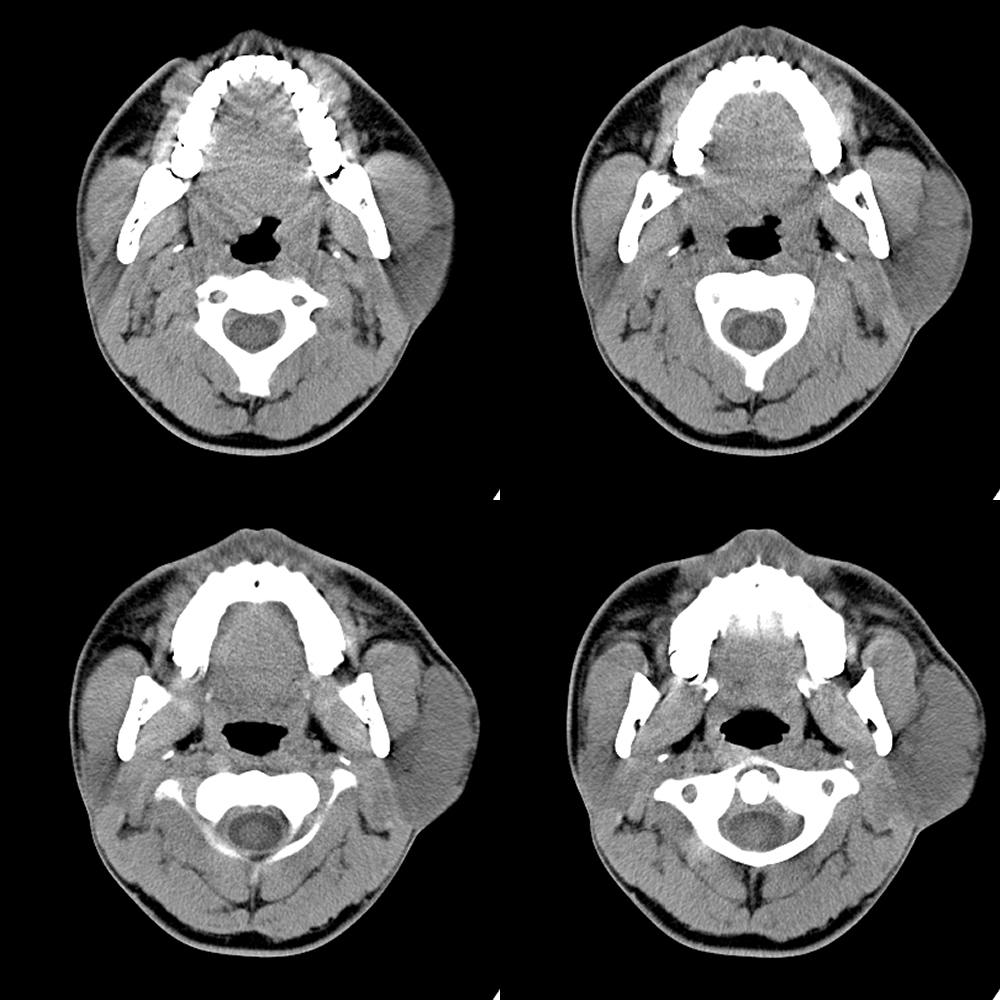

左侧腮部等低密度肿块影,结构较疏松,与咬肌分界清,皮下脂肪间隙清晰,考虑良性病变。建议增强扫描。

淋巴管瘤还是血管瘤,建议增强